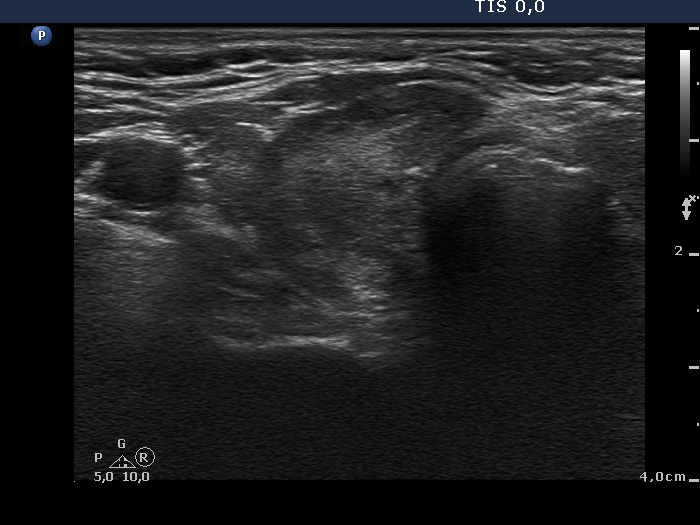

Third examination 18 months after initial examination (third row):

Clinical data: Another relapse of hyperthyroidism occurred 3 months ago. Thereafter, the dose of thyrostatic was increased.

Palpation: unchanged.

Result of blood test: subclinical hyperthyroidism (TSH 0.03 mIU/L, FT4 18.1 pM/L).

Ultrasonography: The pattern was the same.

Fourth examination 21 months after initial investigation (fourth and fifth rows):

Clinical presentation: The patient requested a second opinion. Multiple nodules including a suspicious one in the right lobe were described in another institute. Scintigraphy diagnosed multiple "cold" and warm" nodules in both lobes. Surgery was advised. The surgeon asked aspiration cytology of the hypoechogenic nodule described as suspicious on ultrasonography.

Results of blood tests: euthyroidism on daily 25 mg methimazole (TSH 3.78 mIU/L, FT4 10.9 pM/L).

Ultrasonography: unchanged.Cytology was performed from the hypoechogenic area in the upper part of the right thyroid.

Cytological diagnosis: benign pattern corresponding to previous dysfunction and isotope therapy.

The patient underwent total thyroidectomy. Histopathology disclosed diffuse goiter corresponding to Graves' disease and focal lymphocytic thyroiditis. There were no nodules.

Comment. It is worth analyzing the echo pattern of the thyroid. The small hypoechogenic area in the right lobe changed neither in size nor is shape nor in vascularization over 11 months.